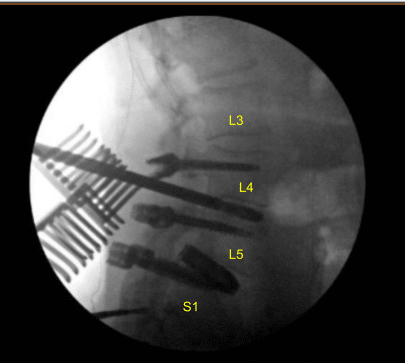

Intraoperative CT scan was obtained. Data was transferred to the neuronavigation computer. Accuracy was verified. Stereotactic image-guided neuronavigation techniques were used to reposition and replace the new pedicle screw at L4 on the right side in a proper position.

The remaining pedicle screws on the left at L4 and bilateral L5 were replaced with new pedicle screws slightly upsized. A tighter fix was achieved. Next, we placed the new pedicle screws at L3 bilaterally decorticating with electric high-speed drill, cannulating with navigated pedicle finder, palpating for breaches, measuring the depth, under tapping by 1 mm and placing the pedicle screws in a usual manner without difficulty. Neuromonitoring signals were stable.

Next, an intraoperative CT scan was obtained showing the correct position of all the screws. Next, we performed L3-4 laminectomy using Leksell rongeurs collecting autograft for morselization for arthrodesis, exposing hypertrophic ligamentum flavum which was retracted in a piecemeal fashion with Kerrison rongeurs.